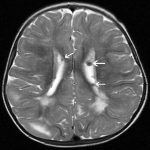

Xơ cứng củ (Tuberous Sclerosis) là một bệnh lý thần kinh da đặc trưng bởi các thay đổi hamartoma trong não, thận, phổi, da, tim và các cơ quan khác. Bệnh xơ cứng củ cũng được biết là bệnh Bourneville, tên một bác sĩ người Pháp, được mô tả bệnh vào năm 1880. Nó là bệnh di truyền bởi gen trội trên NST thường. Tam chứng lâm sàng của bệnh xơ cứng củ bao gồm động kinh, u tuyến bả (u sợi mạch vùng mặt) và chậm phát triển trí tuệ…